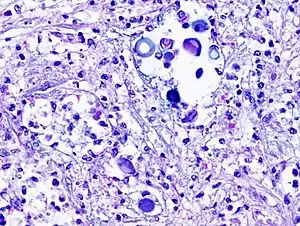

Biopsy

A special stain may be needed to see the cryptococcus capsule.[33]

Mucicarmine stain: bright pink cryptococcosis capsule[33]

Field stain: thick cryptococcosis capsule

H&E stain: histiocytic penumonia_Alcian_blue-PAS.jpg.webp)